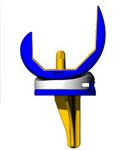

Protesi di ginocchio

Quando il quadro clinico è più grave, siamo di fronte ad una artrosi diffusa. Il trattamento consiste nel sostituire la cartilagine irreversibilmente malata con protesi di nuova generazione in titanio e prevede la sostituzione dell’osso degenerato con mascherine di metallo più o meno grandi in base alla gravità del quadro.

Quando il quadro clinico è più grave, siamo di fronte ad una artrosi diffusa. Il trattamento consiste nel sostituire la cartilagine irreversibilmente malata con protesi di nuova generazione in titanio e prevede la sostituzione dell’osso degenerato con mascherine di metallo più o meno grandi in base alla gravità del quadro.

Nel ginocchio si parla di protesi monocompartimentali quando si sostituisce solo una parte del ginocchio, mediale o laterale; di protesi totali o artroprotesi quando si sostituisce tutta l’articolazione con o senza la protesizzazione della rotula.